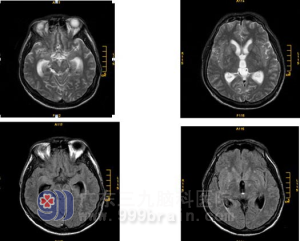

4.頭顱CT或MRI可以顯示雙側腦室對稱性擴大,第三腦室及第四腦室也擴大,腦萎縮。連續顱內壓監護可發現患者熟睡後的眼動期出現顱內壓升高現象,據此可與腦萎縮引起的老年性痴呆相鑑別。腰椎穿刺示腦脊液壓力正常,CSF檢查正常。

1.頭顱CT或MRI可以顯示雙側腦室、第三腦室及第四腦室擴大,腦萎縮。